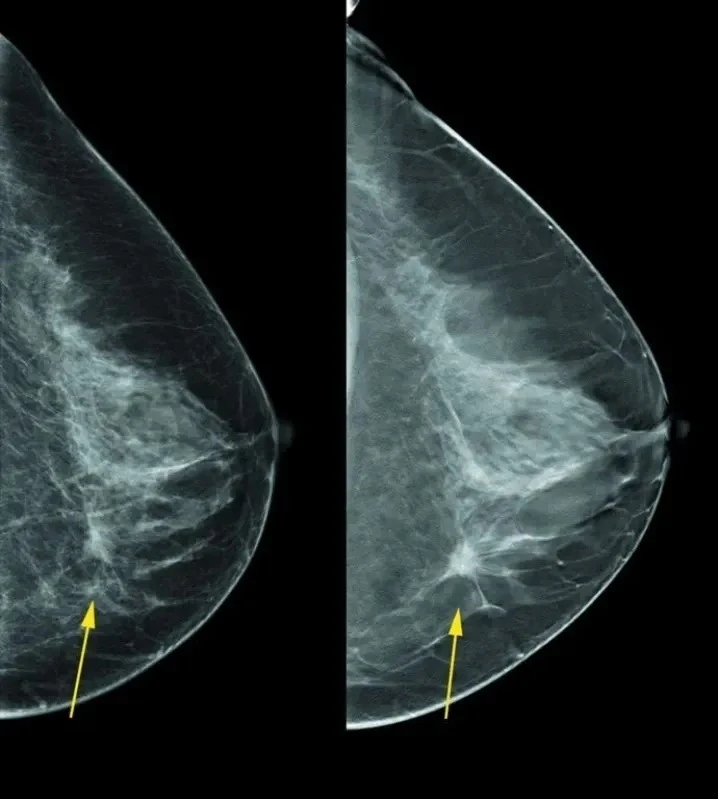

A clínica ginecológica é uma especialidade médica que visa a prevenção, diagnóstico e tratamento das doenças relacionadas ao sistema reprodutor feminino. Essa área da medicina é de extrema importância para a saúde e bem-estar da mulher, e a Clinica Bem Estar oferece serviços de qualidade para atender as necessidades ginecológicas de suas pacientes. Com uma equipe de profissionais altamente capacitados e equipamentos de última geração, a Clinica Bem Estar oferece exames preventivos, diagnósticos precisos e tratamentos adequados para diversas patologias ginecológicas. Não deixe sua saúde em segundo plano, entre em contato com a Clinica Bem Estar e solicite uma cotação para cuidar do seu bem mais precioso: a sua saúde.